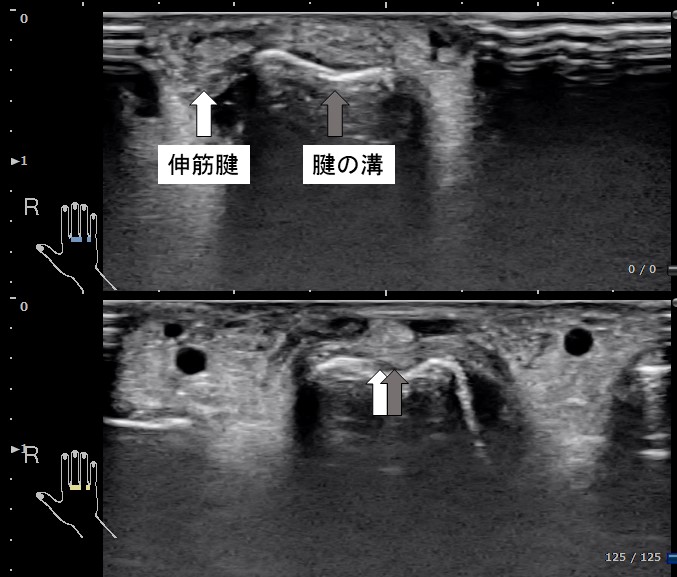

超音波エコーで観察された画像をお示しします。上図が屈曲時、下図が伸展時の中指MP関節部の腱と腱溝の関係を示します。屈曲すると腱溝から腱が外れてしまいます。